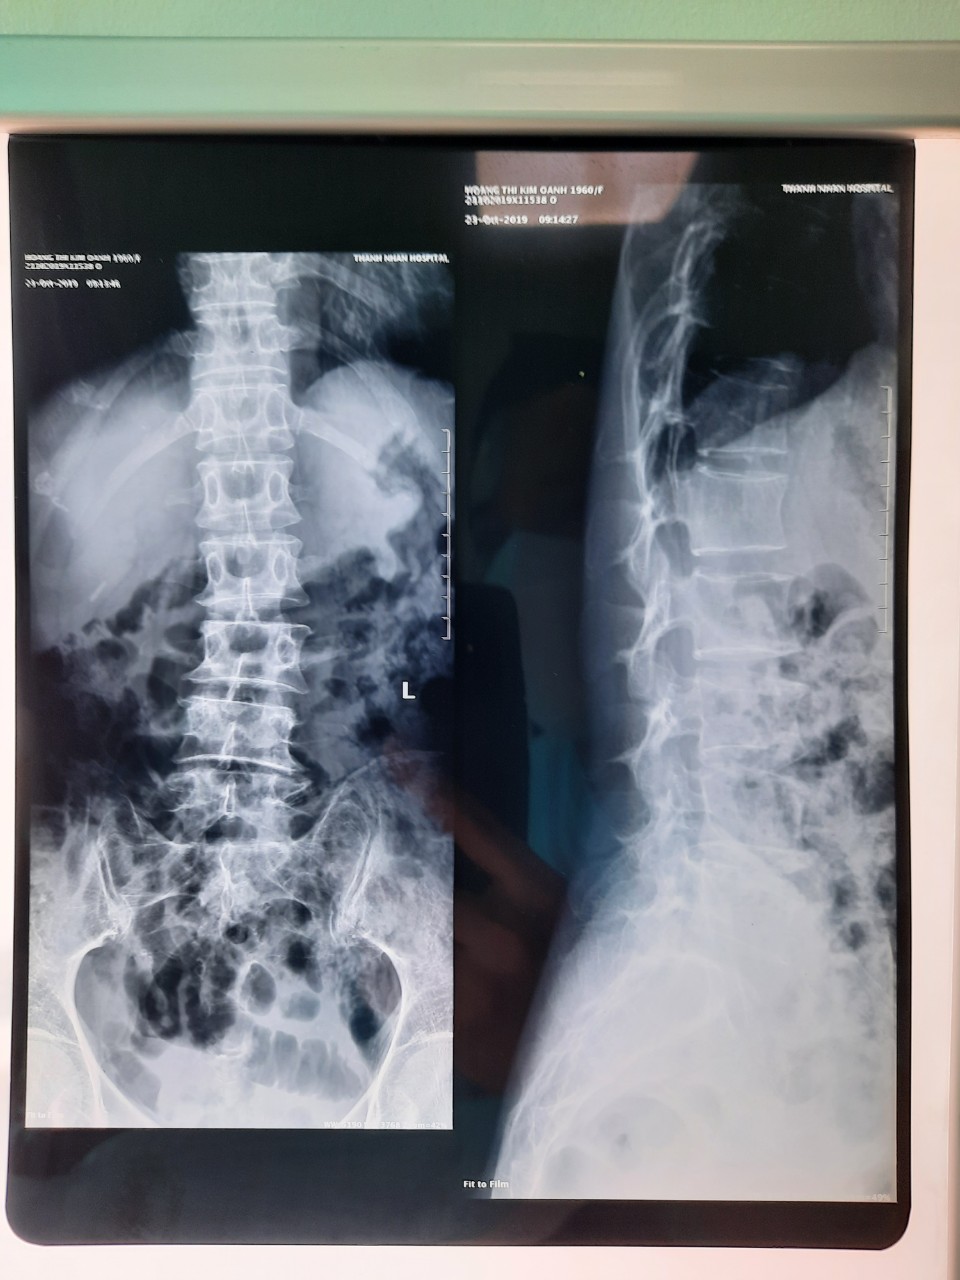

Cơ Xương Khớp, Cột Sống, Đĩa Đệm 06/02/2022 Dịch vụ Chili System Bấm vào để xem “Hình ảnh thực tế Chữa Cơ Xương Khớp, Cột Sống, Đĩa Đệm” tại Phòng Khám YHCT Hải Nam Bài viết liên quan Châm cứu, Bắt mạch, Thuốc Đông Y Đau Cổ, Vai, Tay, Lưng, Chân Gối